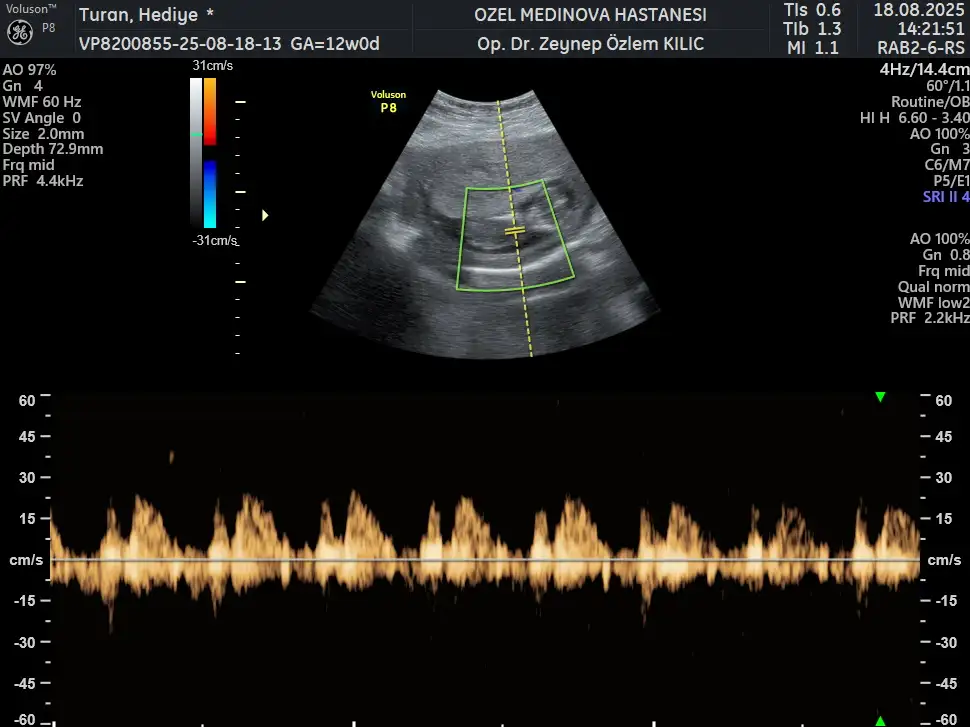

13 haftalık ultrason fotoğrafına göre cinsiyet tahmini?

Bu arkadaşımın 13+3 net değil demişler sizce erkek mi kız mı

Bakın işte burada 3 çizgi🥰 Ama henüz yeni yeni oluştuğu için yanılma payı olabiliyor tabiki😊 Gönlünüzdeki nasip olur inşallah, sağlıcakla